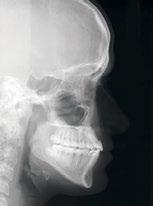

Radiografía Clase III